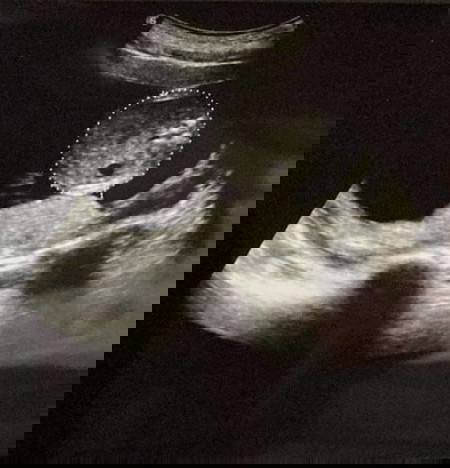

รูปแรกคือช่วงตัวน้องแนวขวางถ้าช่วงหัวจะไม่มีรูๆแบบในภาพ รูๆคืออวัยวะภายในร่างกายน้อง ส่วนรูปสองคือช่วงขาน้อง

รูปแรกเหมือนหมอดูความกลมของศรีษะนะคะ รูป2 เหมือนดูกระดูกสันหลังจ้า

ภาพแรกเป็นกะโหลกศีรษะ ภาพสองคือก้นน้องค่ะ